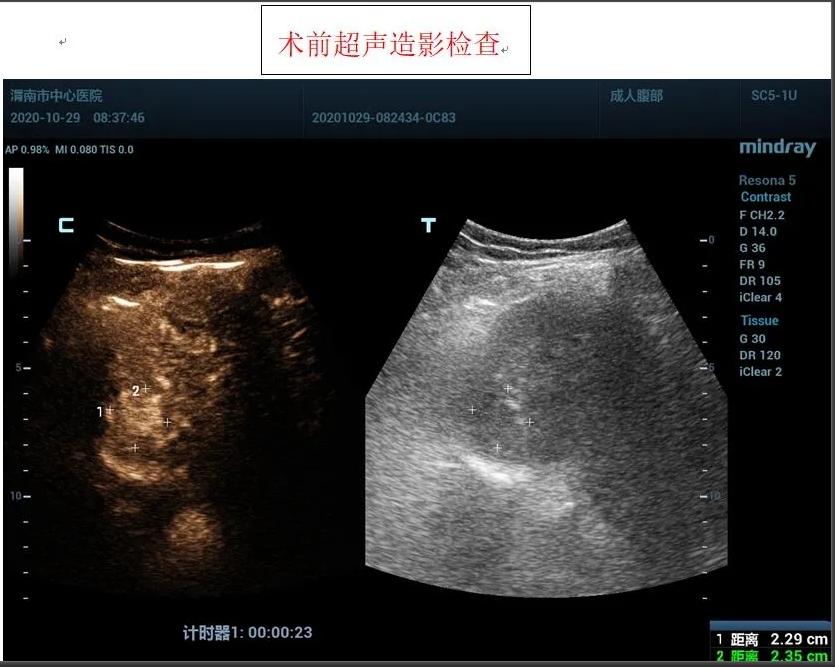

患者女性,71岁,因“糖尿病、肝硬化”在外院进行治疗,住院前进行常规检查,发现肝脏占位性病变,为进一步诊治前来我院,入住感染性疾病科,为进一步明确肝脏肿瘤性质,为患者进行超声造影检查,根据超声造影血流灌注情况,提示肝脏右前叶上段肝细胞癌可能。

患者肿瘤较小且位置较深,紧贴膈肌,且患者伴有冠心病、糖尿病等基础性疾病,感染科李红兵主任在充分评估患者状况后,与超声科刘晓晖主任进行细致讨论,决定对患者行超声引导下微波消融术,因病灶位置特殊,为减少手术风险,特邀西京医院王建宏教授前来进行指导,借助超声造影对肿瘤的部位和血供进行评估和确认后,华玺副主任医师在超声引导下穿刺取活检(病理结果为肝细胞癌)、布针、将消融针娴熟准确地刺入肿块,对肿块进行灭活治疗。

据超声科刘晓晖主任介绍,超声造影技术联合微波消融术可以在术前更明确的反映肿瘤病灶的实际大小及其浸润范围,可将微波治疗范围以超声造影测值作为参考,从而更客观的判断肿瘤病灶大小及周围浸润情况,确认需治疗的范围,同时可以使用超声造影在微波消融术中进行检测引导,术后通过超声造影确认肿瘤是否完全灭活。该方法与传统外科手术相比创伤小,手术时间短,术中痛苦小,并发症极少;术后恢复快,缩短了住院时间,江南在线体育超声科将超声造影技术与微波消融术联合使用,为患者带来了新的治疗希望。